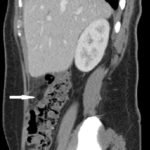

Fitz-Hugh Curtis syndrome (FHCS) is a rare sequela of pelvic inflammatory disease that must be included on the differential in patients with abdominal pain, particularly if they have risk factors for sexually transmitted infections. In this case, a 25-year-old female with a past history of Chlamydia presented to the emergency department with vaginal discharge and right upper quadrant pain. Complete blood count showed a mild leukocytosis, and computed tomography demonstrated fat stranding inferior to the liver and along the right colon. The patient was diagnosed with Fitz-Hugh Curtis syndrome and admitted for intravenous (IV) antibiotics. After 48 hours of IV antibiotics she was discharged with a 14-day course of doxycycline and metronidazole. Multiple bacterial species have been implicated in FHCS, including but not limited to Chlamydia trachomatis, Neisseria gonorrheae, Mycoplasma genitalium, Peptostreptococcus spp., and Prevotella spp. Therefore, careful consideration should be given to the choice of antimicrobial treatment.